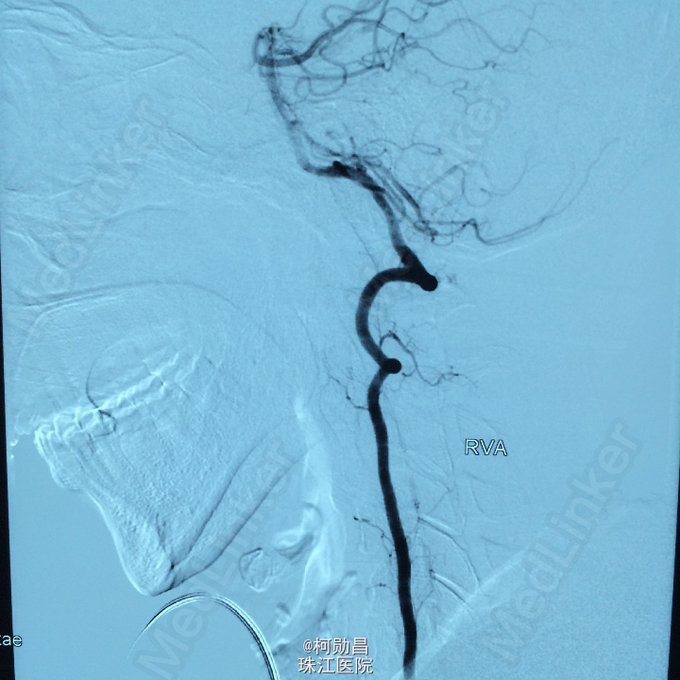

查体:痉挛性截瘫,肌力 4/5 级,马鞍区感觉减退,肛门括约肌张力下降, 腱反射活跃。 辅助检查:腰椎穿刺脑脊液检查示脑脊液蛋白 53mg/dL,葡萄糖 59mg/dL,细胞学检查可见成熟的淋巴细胞,寡克隆区带阴性,免疫球蛋白 IgG 指数为 0.58。布氏杆菌、梅毒、脑脊液 / 血清血管紧张素转换酶水平、结核杆菌聚合酶链反应、单纯疱疹病毒、EB 病毒、水痘 - 带状疱疹病毒,包柔螺旋体(莱姆病)血清学检测均为阴性。结合患者的脊髓 MRI 表现,初步诊断为脊髓血管畸形

诊断:硬脊膜动静脉瘘 处理:予全麻下行栓塞治疗,选择予 withn-butyle-2-cyanoacrylate(医用胶)完全闭塞 。